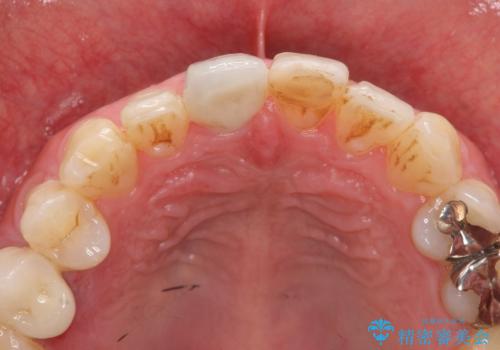

前歯の変色を改善!セラミック治療

- 前歯の変色が気になり審美障害の改善を求めて来院されました。

根管治療に伴う歯の色調変化はよく見られる所見です。

セラミッククラウン製作を行い審美性の改善を計画します。

周囲の歯の色調に合わせた、自然なセラミック治療を行うことができましt。